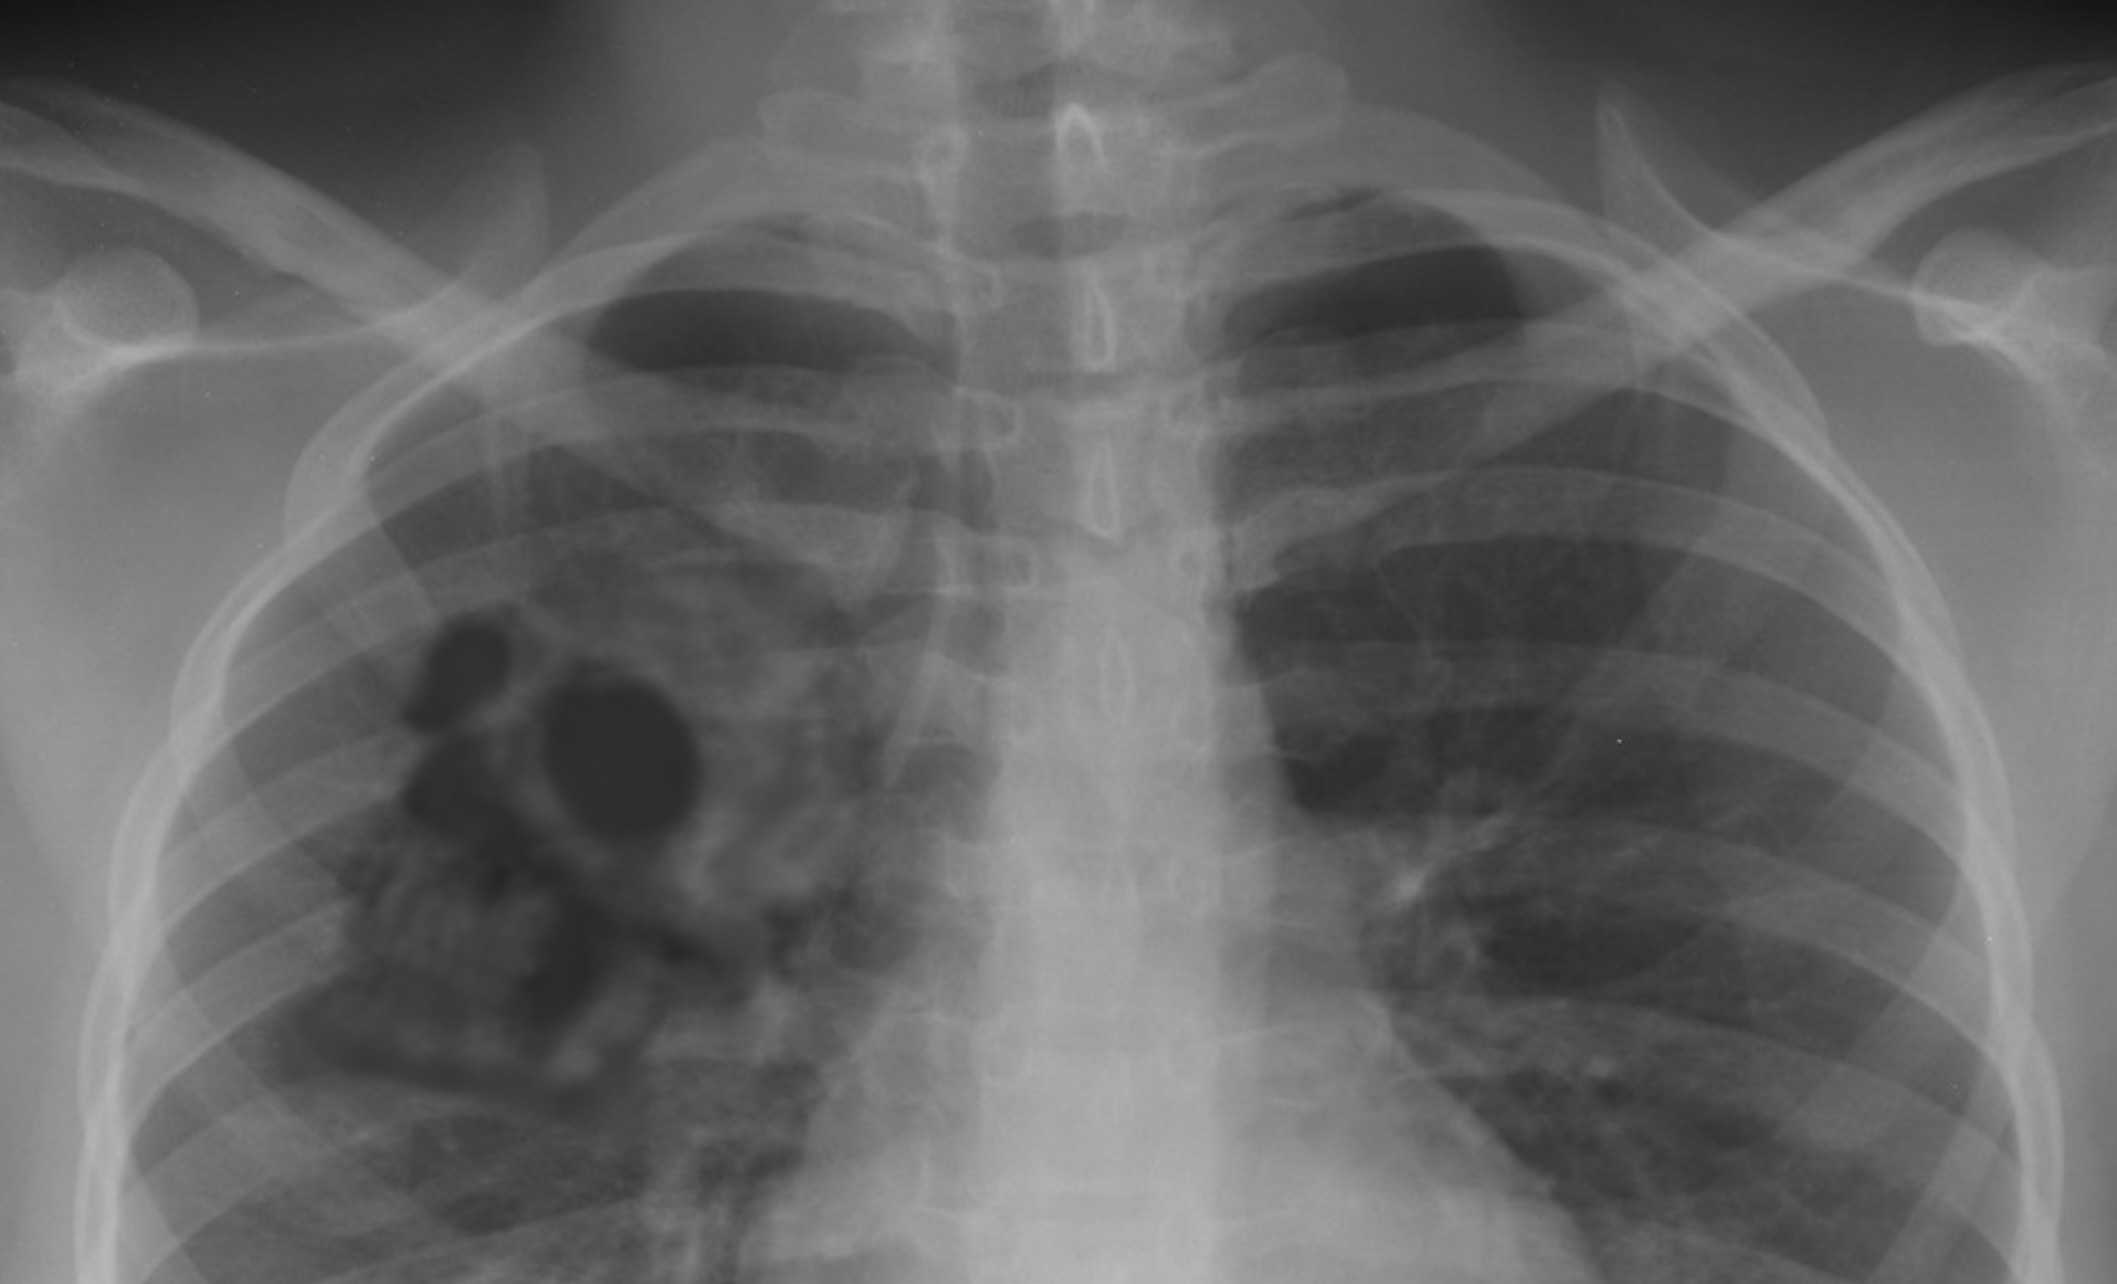

描述:SCP-3008-JP指生成在人肺中的大虾夷盘扇贝(atinopecten yessoensis),目前所确认的最大大小为七厘米。已确认SCP-3008-JP可以以任何满足条件的人类个体为对象生成。

生成有SCP-3008-JP的人类个体(下称对象)在此类通常致命的情况下仍可正常生存,此外,其肺活量和其他肺部机能均与正常情况无异。基金会曾尝试通过解剖对象的手段分离出SCP-3008-JP,但其在接触到外界的极短时间内便会被破坏而形成粉末,故目前没有任何成功得到完整项目的实例。

备注1:于2002/9/26,一位███内科医院的定期访院39岁男性患者被临时拘留。在被拘留之前,对象于同一家医院被确诊肺癌。鉴于先前访院时X光照片显示其肺部结节影肥大化并形成异常轮廓,因此本院的医生以其为罕见病例向日本呼吸科学会共享,并以此引起了基金会的注意。依据若干处相似点,对象被记录为SCP-3008-JP的近似病历。

尽管此名男性并非教职员工,但长年作为火葬场职员工作,并主要承担火葬炉清理任务。从此便可注意到其具有长期吸入了含钙粉尘的可能。已决定将对象释放,并同时对对象进行一年两次的定期检查,以进行跟踪观察1。相关职员应在每次定期检查后更新附加于此文档的X光照片。

2027/6/15 第48回 定期检查